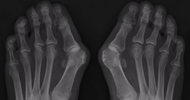

What is a Hallux Valgus?

A Hallux Valgus is a progressive foot deformity where the big toe leans toward the other toes. This pushes the joint at the base of the toe outward, causing a painful, often inflamed bunion. A hallux valgus can lead to pain when walking, difficulty finding suitable shoes, and foot instability.